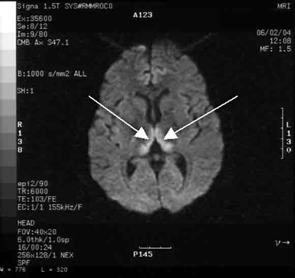

Haematological and biochemical test results were largely normal, but her serum levels of creatinine (0.04 mmol/L; normal range [NR], 0.05–0.10 mmol/L) and urea (2.2 mmol/L; NR, 2.5–6.1 mmol/L) were slightly low, and her INR (international normalised ratio) was 2.0 (NR, 0.8–1.2). There were also some elevated levels in her liver function test results: γ-glutamyl transferase, 60 U/L (NR, < 50 U/L); alanine aminotransferase, 486 U/L (NR, < 55 U/L); and bilirubin, 32 U/L (NR, 0–19 U/L). Cerebrospinal fluid (CSF) examination and magnetic resonance imaging (MRI) were also undertaken to exclude intracranial causes. The CSF findings were normal, but the MRI revealed bilateral thalamic lesions (Figure 2).

Given the new clinical features and her MRI result, a diagnosis of Wernicke’s encephalopathy was made. Thiamine deficiency was suspected to be secondary to hyperemesis gravidarum. Interestingly, her serum thiamine level was only marginally low at 64 nmol/L (normal range, 66–200 nmol/L). Therapy with pyridoxine, folic acid and intravenous thiamine replacement was commenced.

She made a rapid clinical recovery. Visual acuity returned to normal within 3 days and her ataxia, gaze limitation and neuropathy improved. Repeat MRI imaging 7 days later showed moderate resolution of the hyperintensities. Our patient went on to successfully deliver a healthy baby girl at 37 weeks’ gestation.

Our case is unusual in that visual deterioration was the first symptom of an evolving thiamine deficiency. There was a delayed presentation of the classical triad of Wernicke’s encephalopathy — ataxia, mental confusion and ocular gaze problems. Moreover, in our case, MRI scanning was able to detect sensitive neurological changes, raising the suspicion of thiamine deficiency. This information was important in prompt treatment of the condition when clinical signs began to emerge. Indeed there are reports of the usefulness of MRI imaging in diagnosing cases of Wernicke’s encephalopathy.7